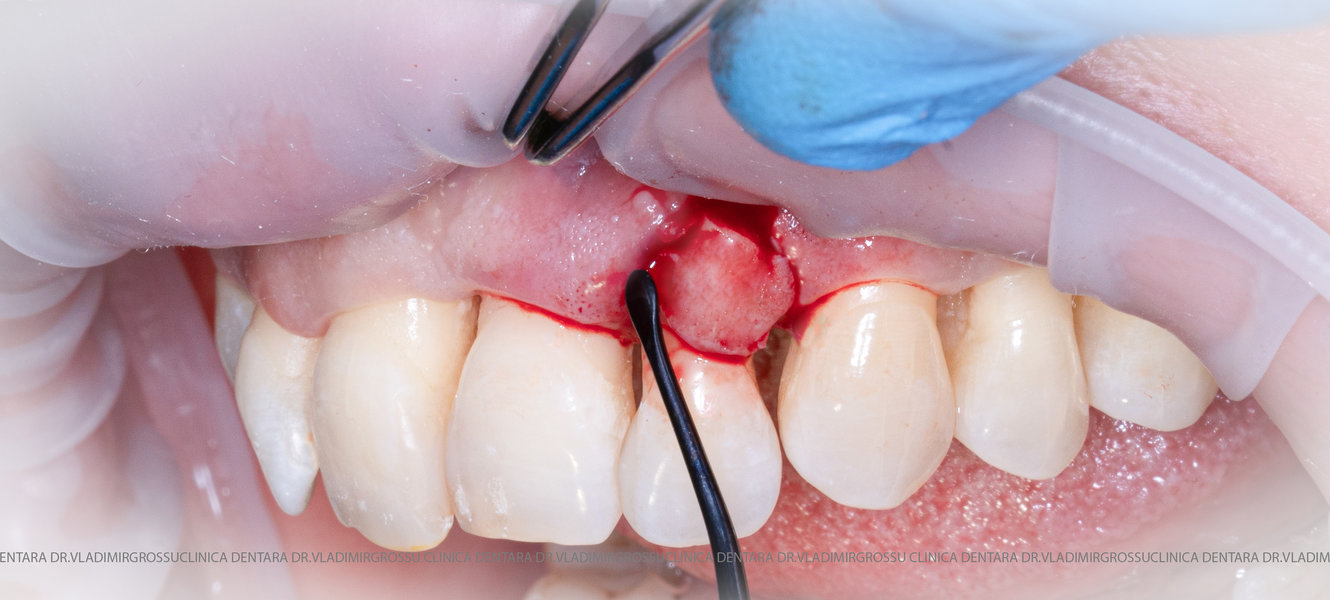

Aditia gingivală este o procedură chirurgicală ce corectează diverse probleme estetice și funcționale, cum ar fi recesiunea gingivală. În implantologia modernă, aditia de țesut moale este utilizată aproape în fiecare intervenție de inserție a implantului dentar pentru a asigura un aspect estetic natural și o bună integrare a implantului în cavitatea bucală.

Adiția osoasă are un rol crucial pentru poziționarea corectă și stabilă a implanturilor dentare. Clinica stomatologică Dr. Grossu din Chișinău promovează o abordare chirurgicală estetică și predictibilă, adaptată fiecărui caz în parte.